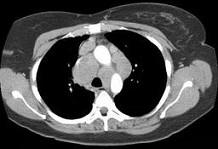

问题 女,33岁,咳嗽,乏力,低热,皮肤有结节,结合CT图像,最可能的诊断是 ( )

选项 A.肺结核 B.霍奇金病 C.非霍奇金病 D.结节病 E.肺癌

答案 D